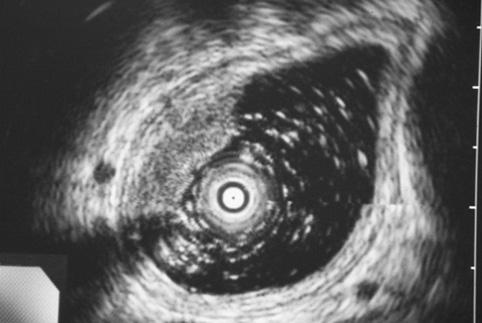

疾患(病理主体)の分類悪性上皮性腫瘍/扁平上皮癌

部位(臓器別)食道/中

検査方法エコー

腫瘍の肉眼分類0型(表在型)/IIa型(IIa+IIc)

病変の最大径(ミリ)15〜19

腫瘍の深達度sm